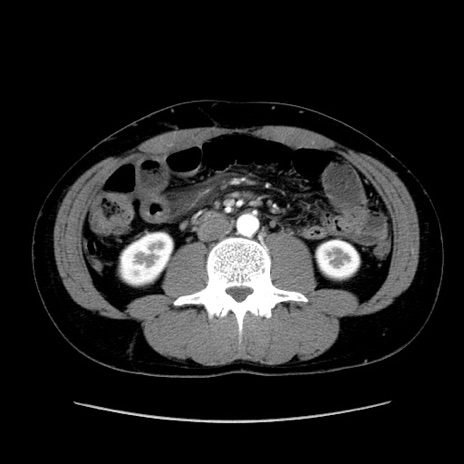

症例36(横断像)

【症例】20歳代 男性

【主訴】心窩部痛

【現病歴】今朝より上腹部痛あり。一旦軽快していたが再度出現したため救急要請。昨日夕に白身の魚を含む刺身を食べた。

【身体所見】BP 136/89mmHg、HR 74/min、BT 37.0℃、腹部:膨満、軟、心窩部に圧痛あり。反跳痛なし、筋性防御なし、腸雑音やや亢進あり。

【データ】WBC 17700、CRP 0.48